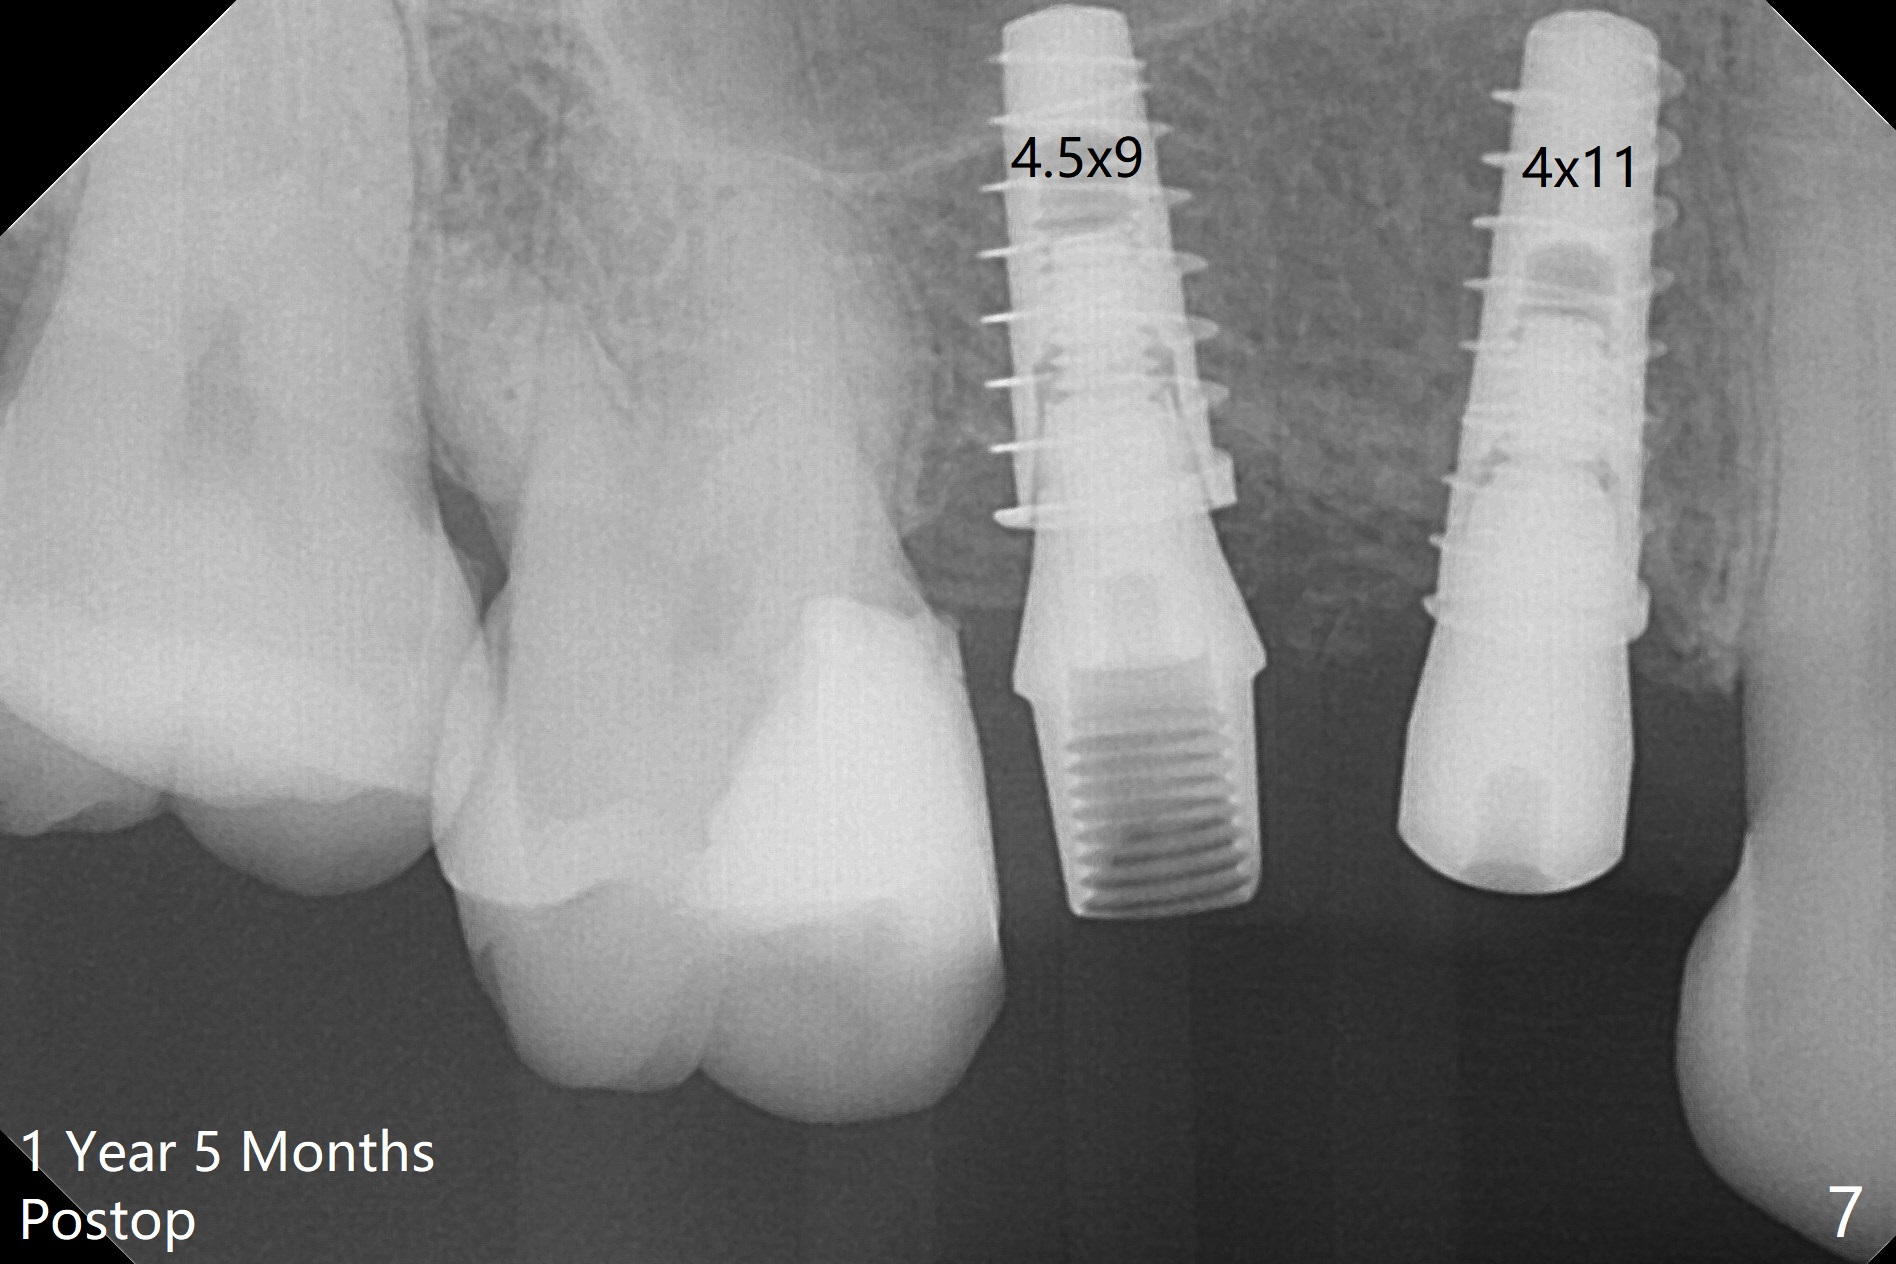

The buccal plate of the socket of #4 is thin and short (Fig.1, 5B (coronal section of the socket) red area) with apical perforation (Fig.5B >). Osteotomy at #4 starts with 1.6 mm drill in the palatal slope (Fig.2 circle; Fig.5C blue arrow), while that at #5 with Magic Split (Fig.2 black line). In fact sinus perforation occurs with the 1.6 mm drill. Osteotomy increases by using Magic Drills sequentially (2.8 and 3.3 mm) at #4 and Magic expander (3.0 mm) and the same Magic Drills at #5 (Fig.3). A 4x11 mm dummy IBS implant is placed with insertion torque of 45 Ncm at #4 with apparently intruding into the sinus (Fig.3). When a 4.5x9 mm implant is placed, the insertion torque is actually reduced (<35 Ncm, Fig.4). As osteotomy or implant diameter enlarges, it shifts buccally with less bone contact buccally (Fig.5D, as compared to Fig.5C)). In brief, once a dummy implant has achieved a reasonably high stability, do not over seat it. A small immediate implant may have more solid bone contact.

At the healed site (#5), insertion torque of a 4x11 mm implant is >50 Ncm (Fig.4). Because of supraeruption of the tooth #28 (Fig.6 arrow), a healing abutment (4x2 mm) is placed at #5 (data not shown), while a pair abutment (4.5x4(2) mm) is placed at #4 (Fig.4,6). In fact a splinted provisional is placed at #4 and 5 with a low occlusal table. There is no apparent bone loss 1 years 5 months postop (Fig.7). In fact the implants either perforate the palaatal or buccal (B) plate, as revealed by CBCT (1 year 6 months postop, immediately post cementation, Fig.8,9). It appears necessary to have guided surgery and smaller implant in the narrow ridge.